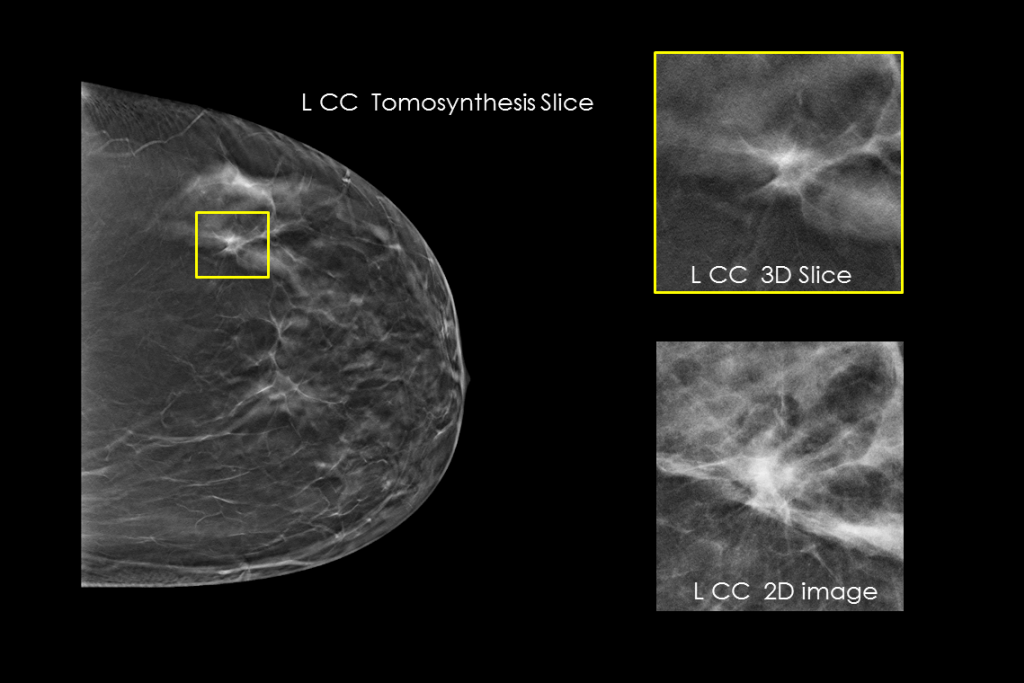

Imágenes clínicas de una mamografía

Imágenes clínicas de una mamografía con una lesión sospechosa